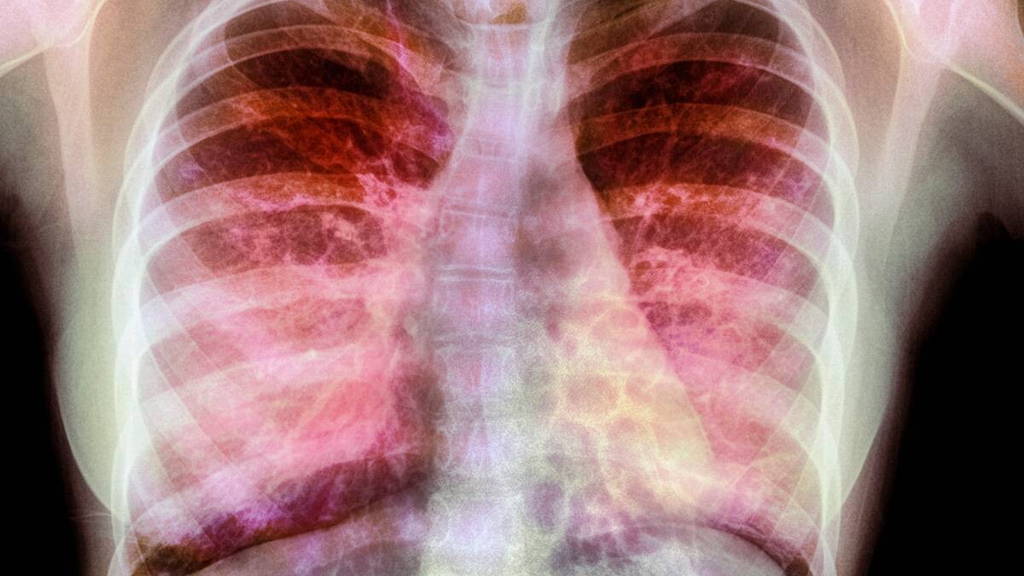

Ruim 40 Europese centra gaan de komende vijf jaar onder leiding van het UMC Utrecht onderzoek doen naar nieuwe behandelingen tegen taaislijmziekte, cystic fibrose. De Europese Commissie heeft hiervoor 6,7 miljoen euro subsidie toegekend. Het onderzoekstraject staat onder leiding van professor Kors van der Ent.

Onderzoek en subsidie zijn bedoeld om nieuwe, gepersonaliseerde behandelingen te realiseren voor Europese CF-patiënten. Nu krijgen veel CF-patiënten alleen symptoombestrijding. “In dit onderzoek willen we specifiekere groepen patiënten gaan behandelen, vooral patiënten die een zeldzaam genetisch profiel hebben”, licht Van der Ent toe. “Op die manier kunnen we gerichter op zoek gaan naar goede medicijnen en behandelingen voor hen.”